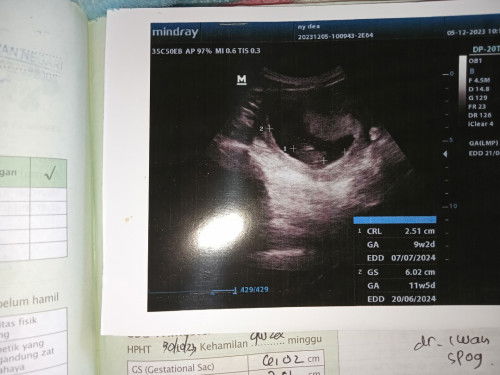

Bunda ada yang sama gak hamil 9 minggu pas di usg muncul 2, tapi yang 1 uda kelihatan janin dan ada detak jantungnya. Yang atas dan agak besar itu kira² apa ya... Apa benar itu seperti miom, trs gimana cara pengobatan nya bund